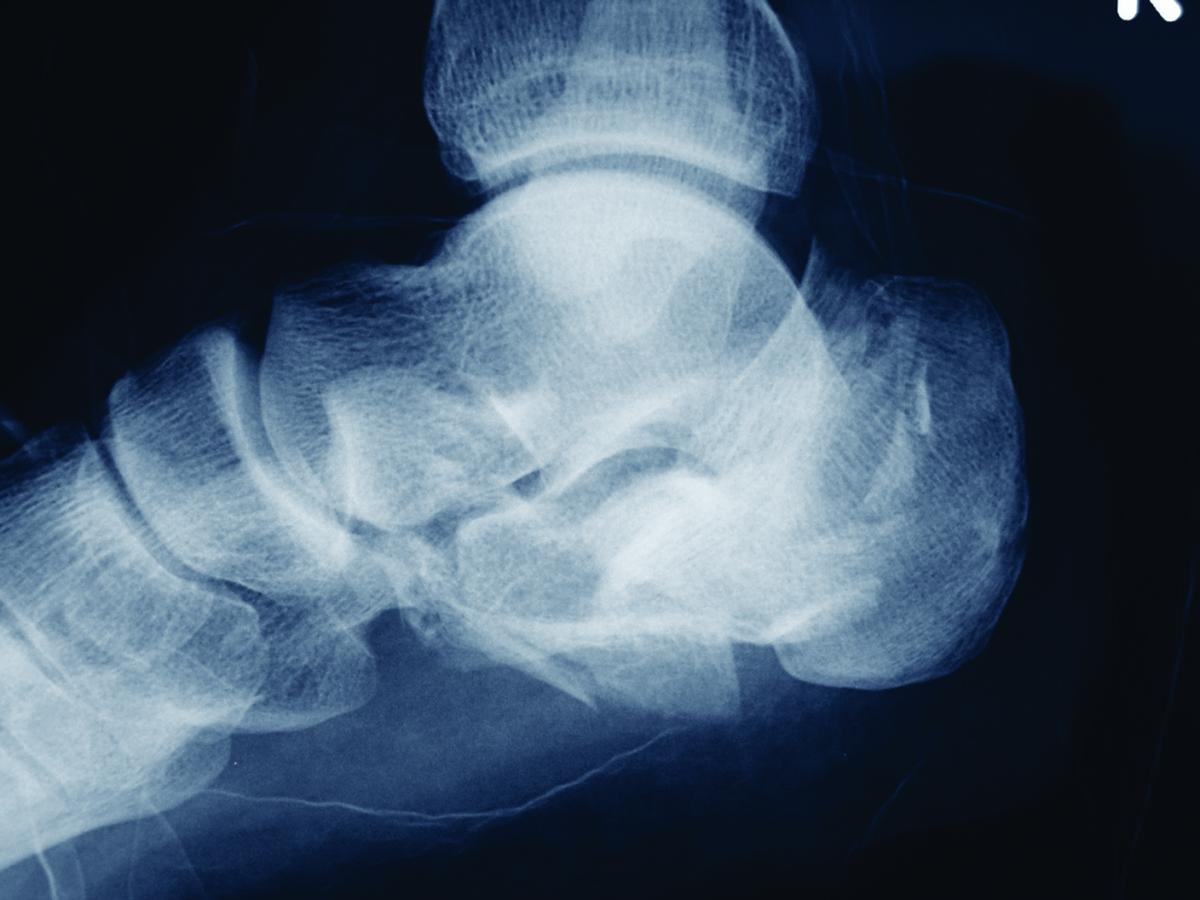

A recent study in the Journal of Foot and Ankle Surgery discourages the use of unmodified Kirschner wires (K-wires) for open reduction and internal fixation (ORIF) of calcaneal fractures, pointing out an incidence of dislocation and migration with the fixation.

Researchers analyzed data from a total of 279 patients who received surgery for displaced intra-articular calcaneal fractures over a 15-year period. The study identified 69 K-wires that surgeons used in 49 patients, finding that a total of 25 K-wires had been lost (buried), 38 had been bent, and six were unmodified straight K-wires. Overall, authors say secondary dislocation occurred with four out of 69 cases in which surgeons used K-wires and K-wire migration occurred in 5.8 percent of the cases. In contrast, the study notes none of the bent K-wires migrated or led to secondary dislocation in the present study.